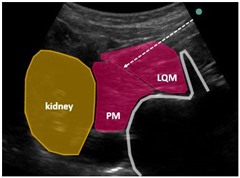

QLB-3はtransmuscular approachです。

つまり腰方形筋を突き破って、筋肉の向こう側に注入します。

さらに、プローブを若干頭側にスライドさせ

腎臓が見えるポジションで行うのがQLB-3のプロトタイプです。

図のように、腰方形筋を貫き

大腰筋の手前もしくは腎臓の手前を狙います。

もちろん、腰方形筋の向こう側にあるtransversalis fasciaは貫かずに、その筋膜内に注入します。